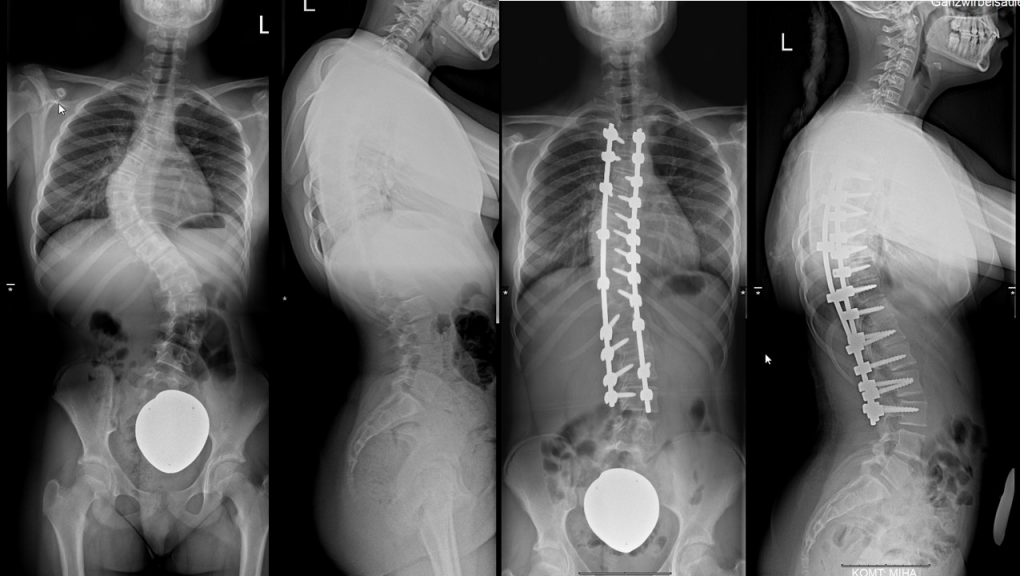

Skoliosetherapie (Chêneau-Korsett, operative Behandlung)

Das Chêneau-Korsett wird bei Patienten angewendet, die sich im Wachstumsalter befinden und an einer progredienten idiopathischen Skoliose leiden. Das Chêneau-Korsett ist asymmetrisch gebaut und bildet neben Druckzonen (Pelotten) auch Freiräume (Expansionszonen).

Beim Bau des Korsetts wird zunächst ein Gipsabdruck angefertigt. Daraus erstellt der Orthopädie-Mechaniker das Korsett mit drei Druckpunkten, um einen aktiven Ausgleich der Fehlhaltung zu erwirken. Wichtig ist eine gleichzeitige muskuläre Stabilisierung der Wirbelsäule, so dass wir unsere Patienten zu einer regelmäßigen sportlichen Betätigung ermutigen. Eine operative Korrektur ist nur bei einer geringen Zahl der Skoliosepatienten notwendig.